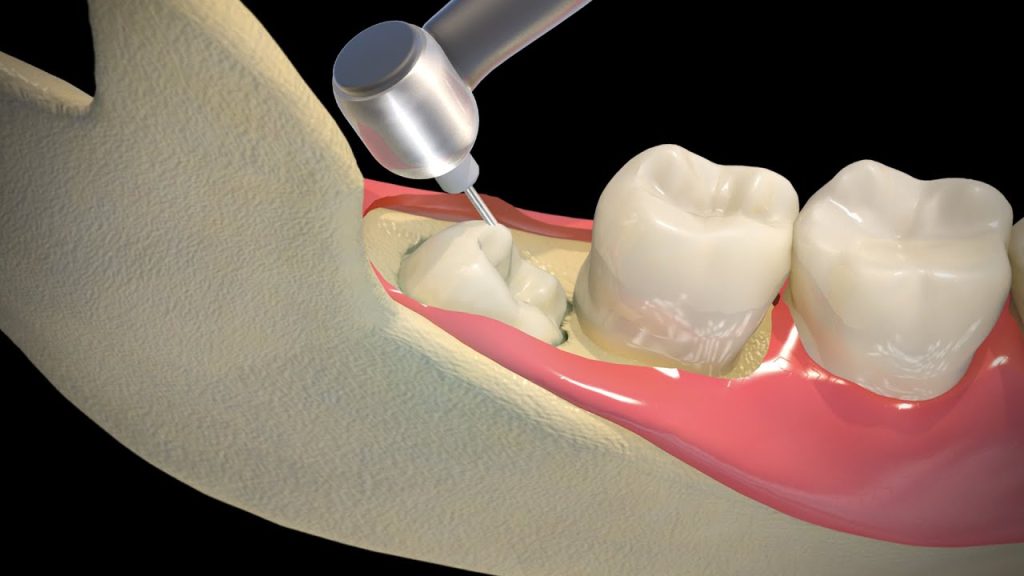

Gentle and Safe Extraction Process

Our dental team uses advanced imaging, local anesthesia, and sedation options to ensure a safe and stress-free extraction. Whether your wisdom teeth are fully erupted or impacted under the gums, we take a gentle approach that minimizes discomfort and speeds up recovery.

Since wisdom teeth erupt later than other molars, there is often not enough room for them to grow properly. This can cause them to push against nearby teeth, become trapped under the gums, or grow at an angle. These issues often lead to discomfort, crowding, or infection if left untreated.